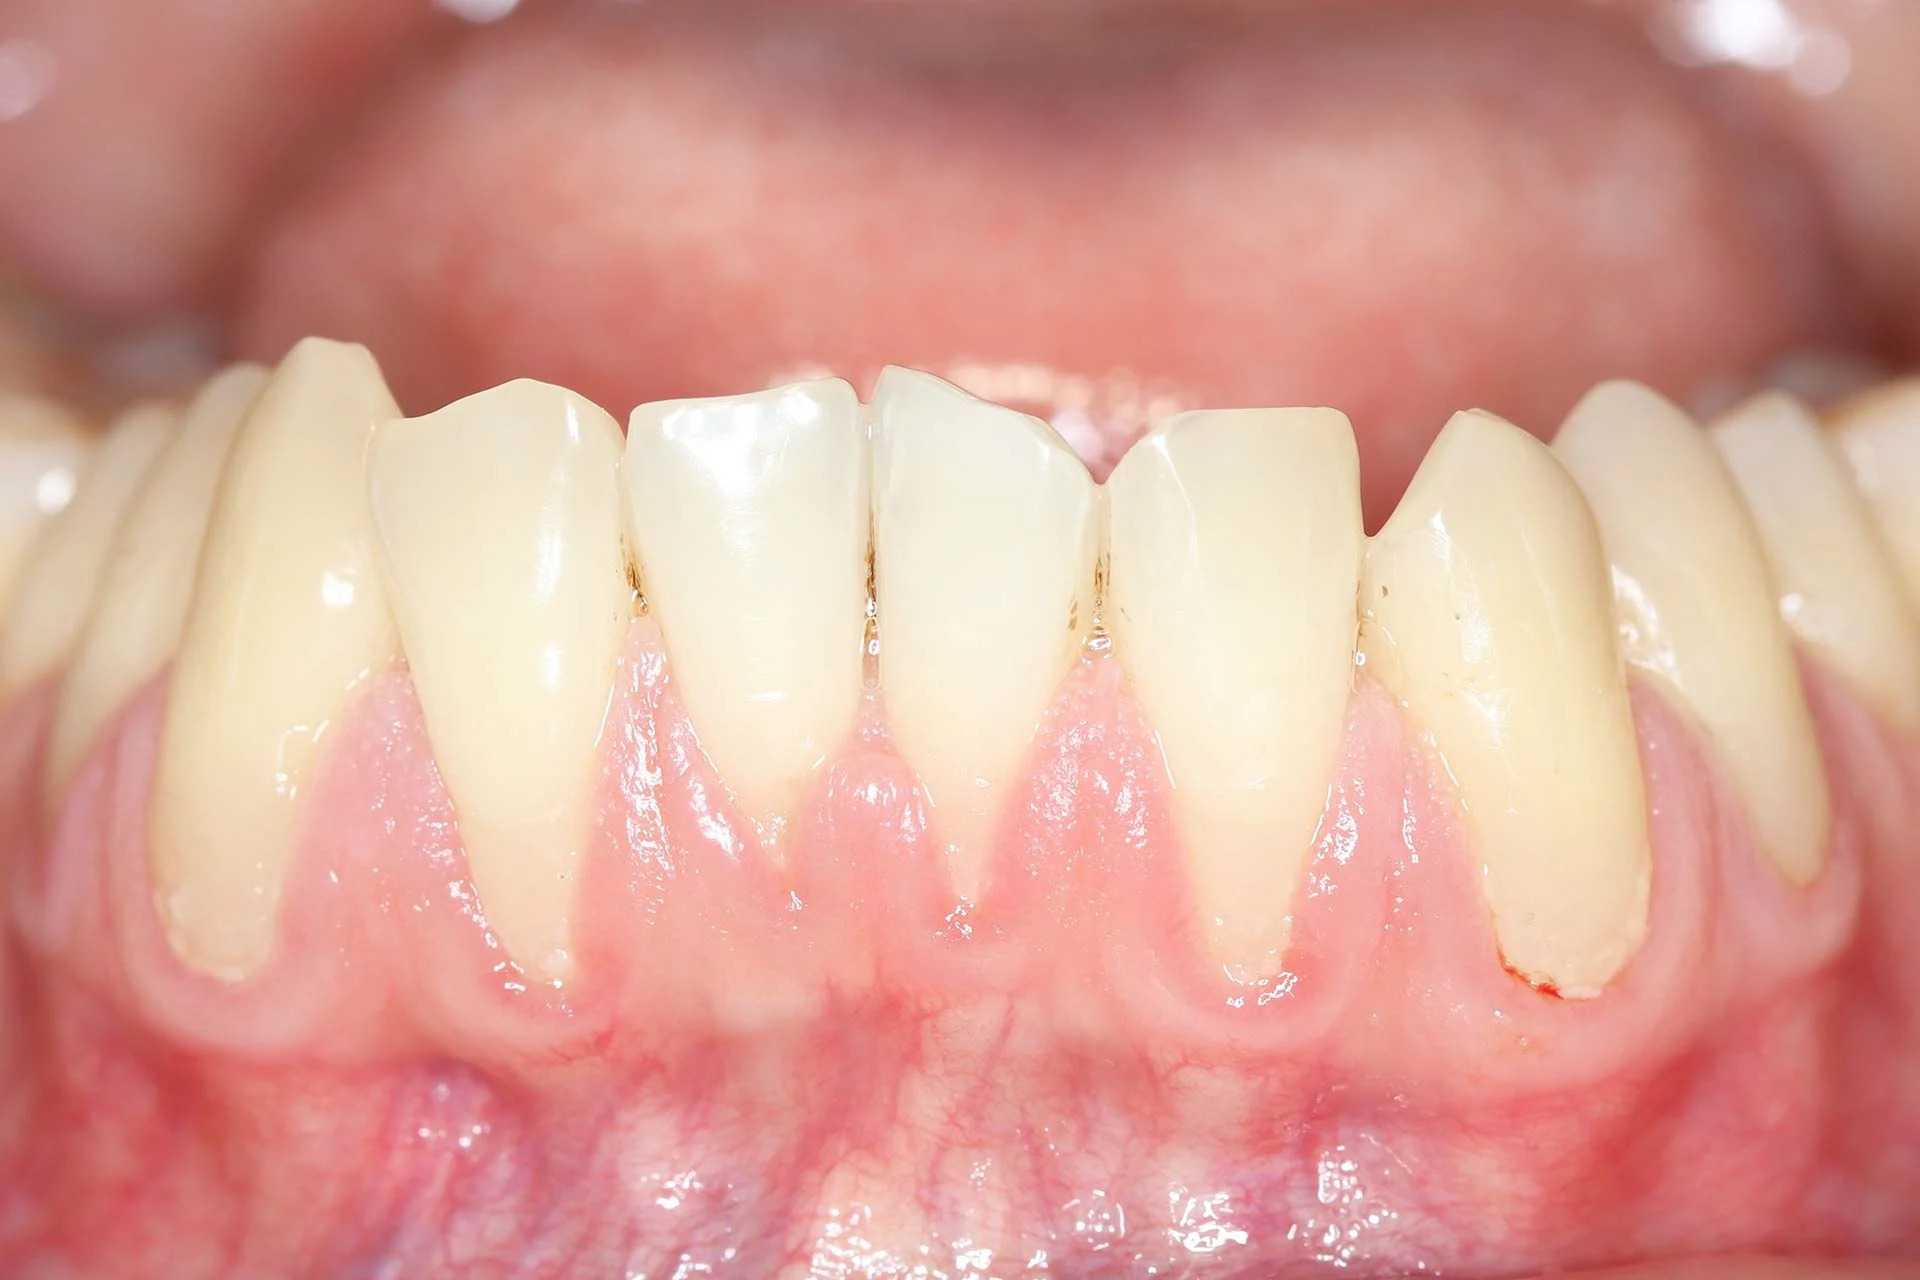

Differenze tra gengiva sana e gengiva ritirata

- Le gengive sane appaiono rosa, compatte e avvolgono i denti come un colletto.

- Le gengive ritirate, al contrario, lasciano visibile una porzione della radice dentale e possono dare l’impressione che i denti siano più lunghi.

- In casi estremi, si notano gengive scollate, pezzi di gengiva che si staccano o addirittura spazi neri tra i denti (tasche gengivali).

Segnali visibili come radici esposte o denti che appaiono più lunghi

- Radici esposte: La caratteristica principale della recessione gengivale è l’esposizione delle radici dei denti, che normalmente sono coperte dalla gengiva. Questo accade quando il tessuto gengivale si ritira, lasciando visibile la parte del dente sotto la linea gengivale. Le radici, non essendo protette dallo smalto, sono molto più sensibili agli stimoli esterni.

- Denti che appaiono più lunghi: Un altro segno visibile di recessione gengivale è la percezione di denti più lunghi rispetto al normale. Questa condizione è particolarmente visibile sui denti anteriori e sui molari. La lunghezza maggiore dei denti è causata dalla ritrazione della gengiva che lascia scoperta una parte del dente.